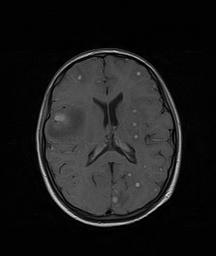

Vista la persistenza del vomito, viene effettuata anche una risonanza magnetica cerebrale (RMN) encefalo con mezzo di contrasto che mostra multiple lesioni cerebrali circolari, alcune con forma ad anello dopo captazione del mezzo di contrasto, compatibili con tubercolomi (Figura 3). Eseguita anche un�ecografia addominale che evidenzia quattro lesioni circolari a livello epatico, anch�esse accordabili con tubercolomi.

Figura 3. Bilateralmente si evidenziano numerosissime lesioni rotondeggianti iso-ipointense in T1, con netto enhancement dopo mdc, delle dimensioni comprese tra 5-7 mm e con edema perilesionale. Diverse di queste lesioni presentano il centro ipointenso in T1, da necrosi caseosa, con impregnazione periferica ad anello dopo mdc; la lesione di dimensioni maggiori � localizzata in sede parietale destra, con marcato edema perilesionale, che causa minima compressione del corno frontale di destra e modesto shift della linea mediana verso sinistra.

I tubercolomi cerebrali sono spesso asintomatici; a seconda della loro localizzazione possono dare segni neurologici focali che sono tuttavia poco frequenti nel bambino. La RMN encefalica rappresenta il gold standard diagnostico: i tubercolomi appaiono come lesioni circolari con forma ad anello dopo captazione del mezzo di contrasto, circondate da edema2.